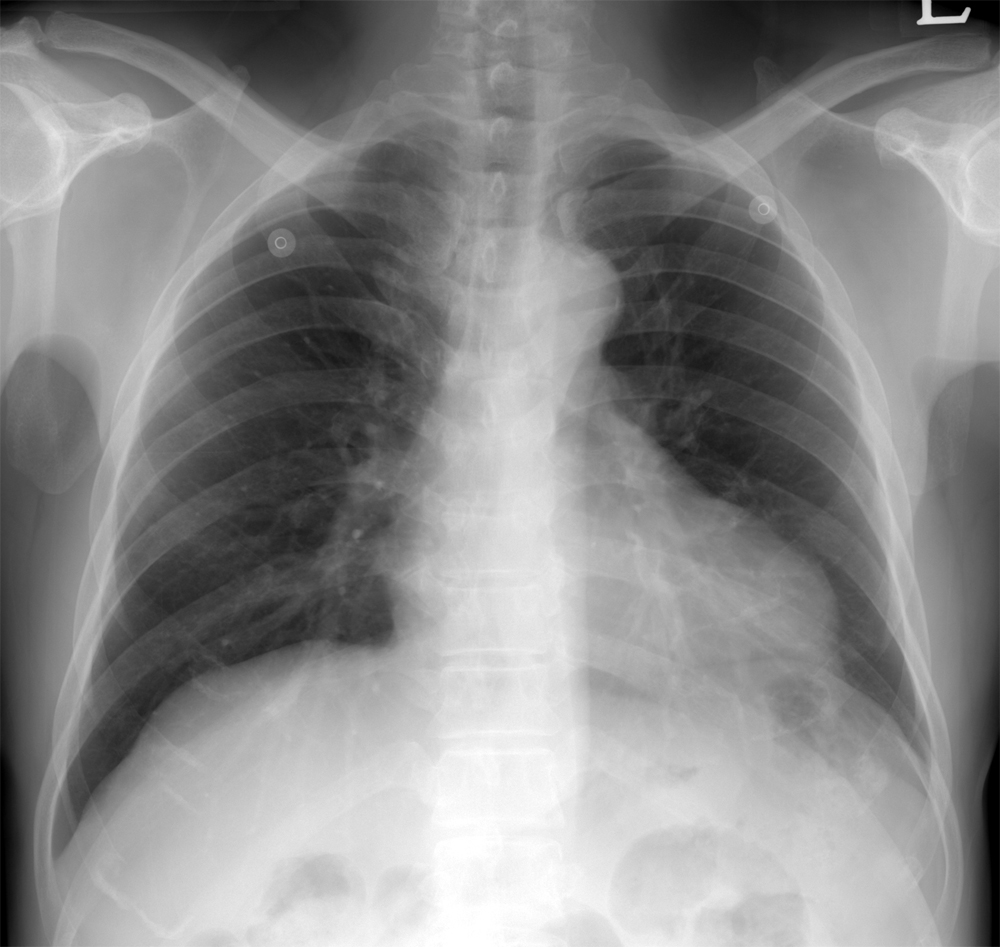

cardiomegaly on x-ray 11/F

Kyungsun Nam, Department of Radiology, Yonsei University College of Medicine

HIT : 16